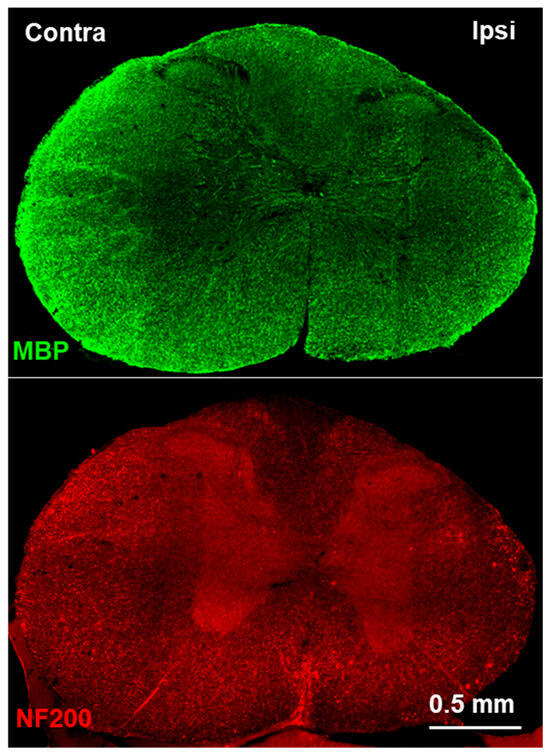

2.4. Immunofluorescence Staining